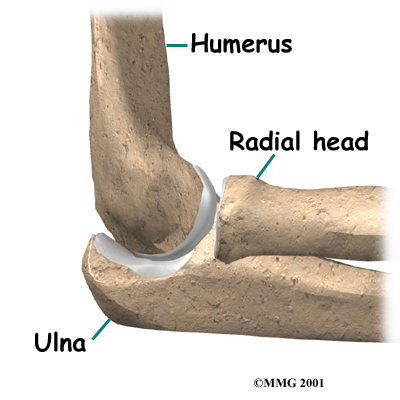

The bones of the elbow are the humerus (the upper arm bone), the ulna (the larger bone of the forearm, on the opposite side of the thumb), and the radius (the smaller bone of the forearm on the same side as the thumb). The elbow itself is essentially a hinge joint, meaning it bends and straightens like a hinge. There is a second joint that makes up the elbow, where the end of the radius (the radial head), meets the humerus.

The bones of the elbow are the humerus (the upper arm bone), the ulna (the larger bone of the forearm, on the opposite side of the thumb), and the radius (the smaller bone of the forearm on the same side as the thumb). The elbow itself is essentially a hinge joint, meaning it bends and straightens like a hinge. There is a second joint that makes up the elbow, where the end of the radius (the radial head), meets the humerus.

This joint is complicated because the radius has to rotate so that you can turn your hand palm up and palm down. At the same time, it has to slide against the end of the humerus as the elbow bends and straightens. This part of the elbow is even more complex because the radius also joins with the ulna to form a joint, and this part of the radius has to slide against the ulna as it rotates the wrist as well. The end of the radius at the elbow is shaped like a smooth knob with a smooth cup at the end to fit on the end of the humerus. The edges are also smooth where it glides against the ulna.

The bones of the elbow are the humerus (the upper arm bone), the ulna (the larger bone of the forearm, on the opposite side of the thumb), and the radius (the smaller bone of the forearm on the same side as the thumb). The elbow itself is essentially a hinge joint, meaning it bends and straightens like a hinge. There is a second joint that makes up the elbow, where the end of the radius (the radial head), meets the humerus.

The bones of the elbow are the humerus (the upper arm bone), the ulna (the larger bone of the forearm, on the opposite side of the thumb), and the radius (the smaller bone of the forearm on the same side as the thumb). The elbow itself is essentially a hinge joint, meaning it bends and straightens like a hinge. There is a second joint that makes up the elbow, where the end of the radius (the radial head), meets the humerus.